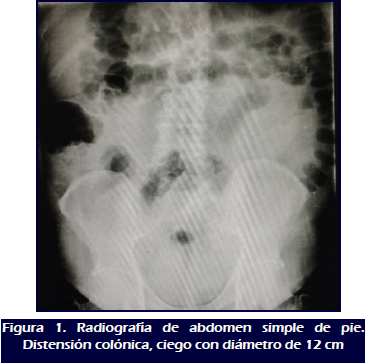

La radiografía de abdomen simple de pie muestra distensión de asas intestinales, con presencia de niveles hidroaéreos y distensión de colon a expensas de ciego (Figura 1). El ecosonograma abdominal documenta dilatación colónica total a predominio de colon derecho y transverso, sin líquido libre en cavidad peritoneal. La tomografía axial computarizada (TAC) con contraste oral informa dilatación severa de colon a expensas de colon derecho. Se ingresa con diagnóstico de abdomen agudo médico: colitis amebiana